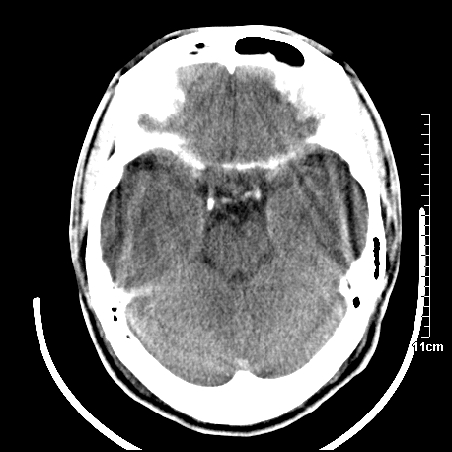

头晕.头痛间断意识恍惚1周 m/21y

4天上述症状加重伴左侧肢体发软,复查ct,

右侧放射冠可见点状低密度,可疑腔隙性梗塞

右側放射冠区改变,建议ct增强或mri检查.

右側额叶、放射冠区灰白质改变,建议ct增强或mri检查

右侧基底节区低密度灶,建议磁共振检查。

右侧放射冠区混杂密度灶,边缘不清,病人较年轻,结合有发热病史,支持感染性病变,建议密切结合临床可抗感染治疗后复查。

右侧颞叶病变定性困难,既然发病急,又有发热,脑脓肿不能除外。

右侧颞叶混杂密度灶,强烈建议:增强ct检查